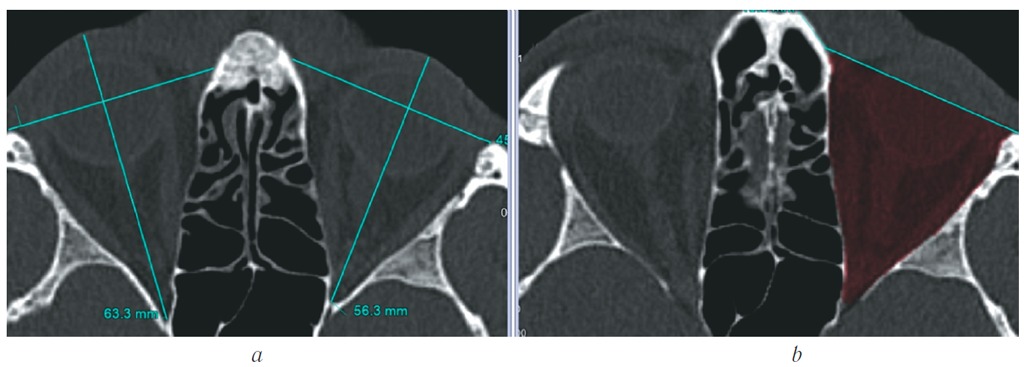

- На изображениях определяли костные границы орбит, по которым будет проходить маркировка. Необходимым условием правильного выполнения исследования является симметричность костных границ для обеих орбит. Для определения наружной границы маркировки проводили линию через всю длину орбиты и перпендикуляр к её длине (построения выполняли сразу для обеих орбит) (рис. 1).

Рис. 1. МСКТ, средняя зона лица, костный режим. Аксиальная реконструкция. Определение наружных границ обит

Fig. 1. MSCT, midface, bone window. Аxial reconstruction. Marking of orbital bone borders